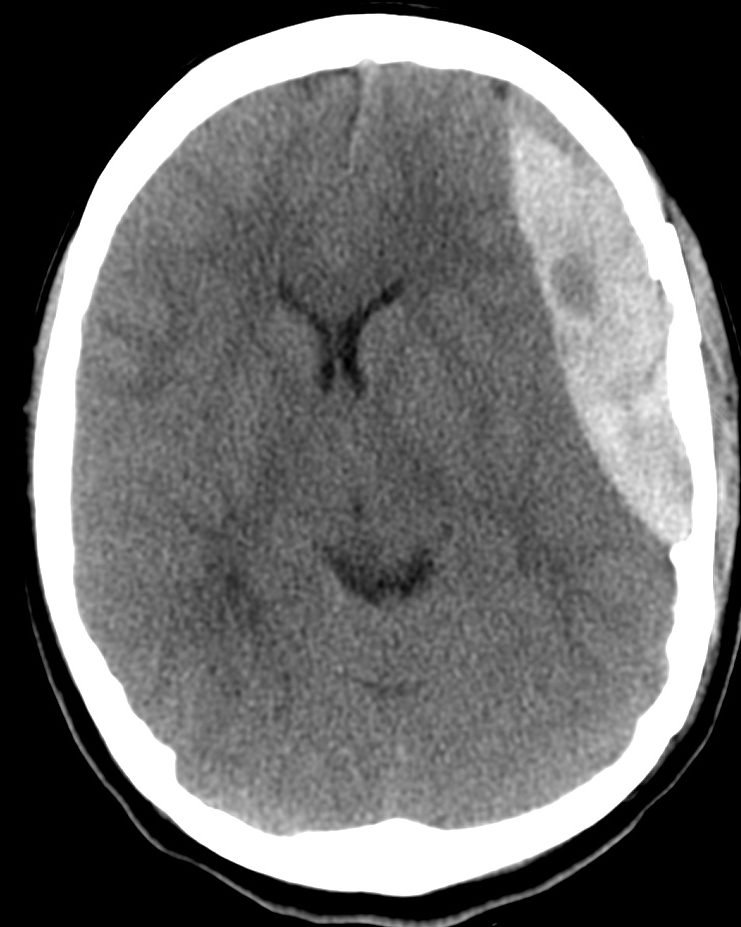

Hematoma Subdural.

- Se localiza entre la duramadre y la aracnoides y suele ser de origen venoso por la disrupción de venas corticales.

- Puede localizarse en punto de golpe y también en el de contragolpe.

- Semiluna hiperdensa (si agudo). Localización: Convexidad > hoz > tentorio

- Cuando son subagudos pasan a ser Isodensos, se identifican porque hay separación del cortex respecto a la tabla interna y efecto masa sin «masa aparente»: colpaso ventricular, desplazamiento de la línea media, etc.

- En estadío crónico puede ser hipodensos.

- Puede cruzar suturas.

- Puede asociar fracturas, contusiones, efecto masas, edema cerebral, HSA.